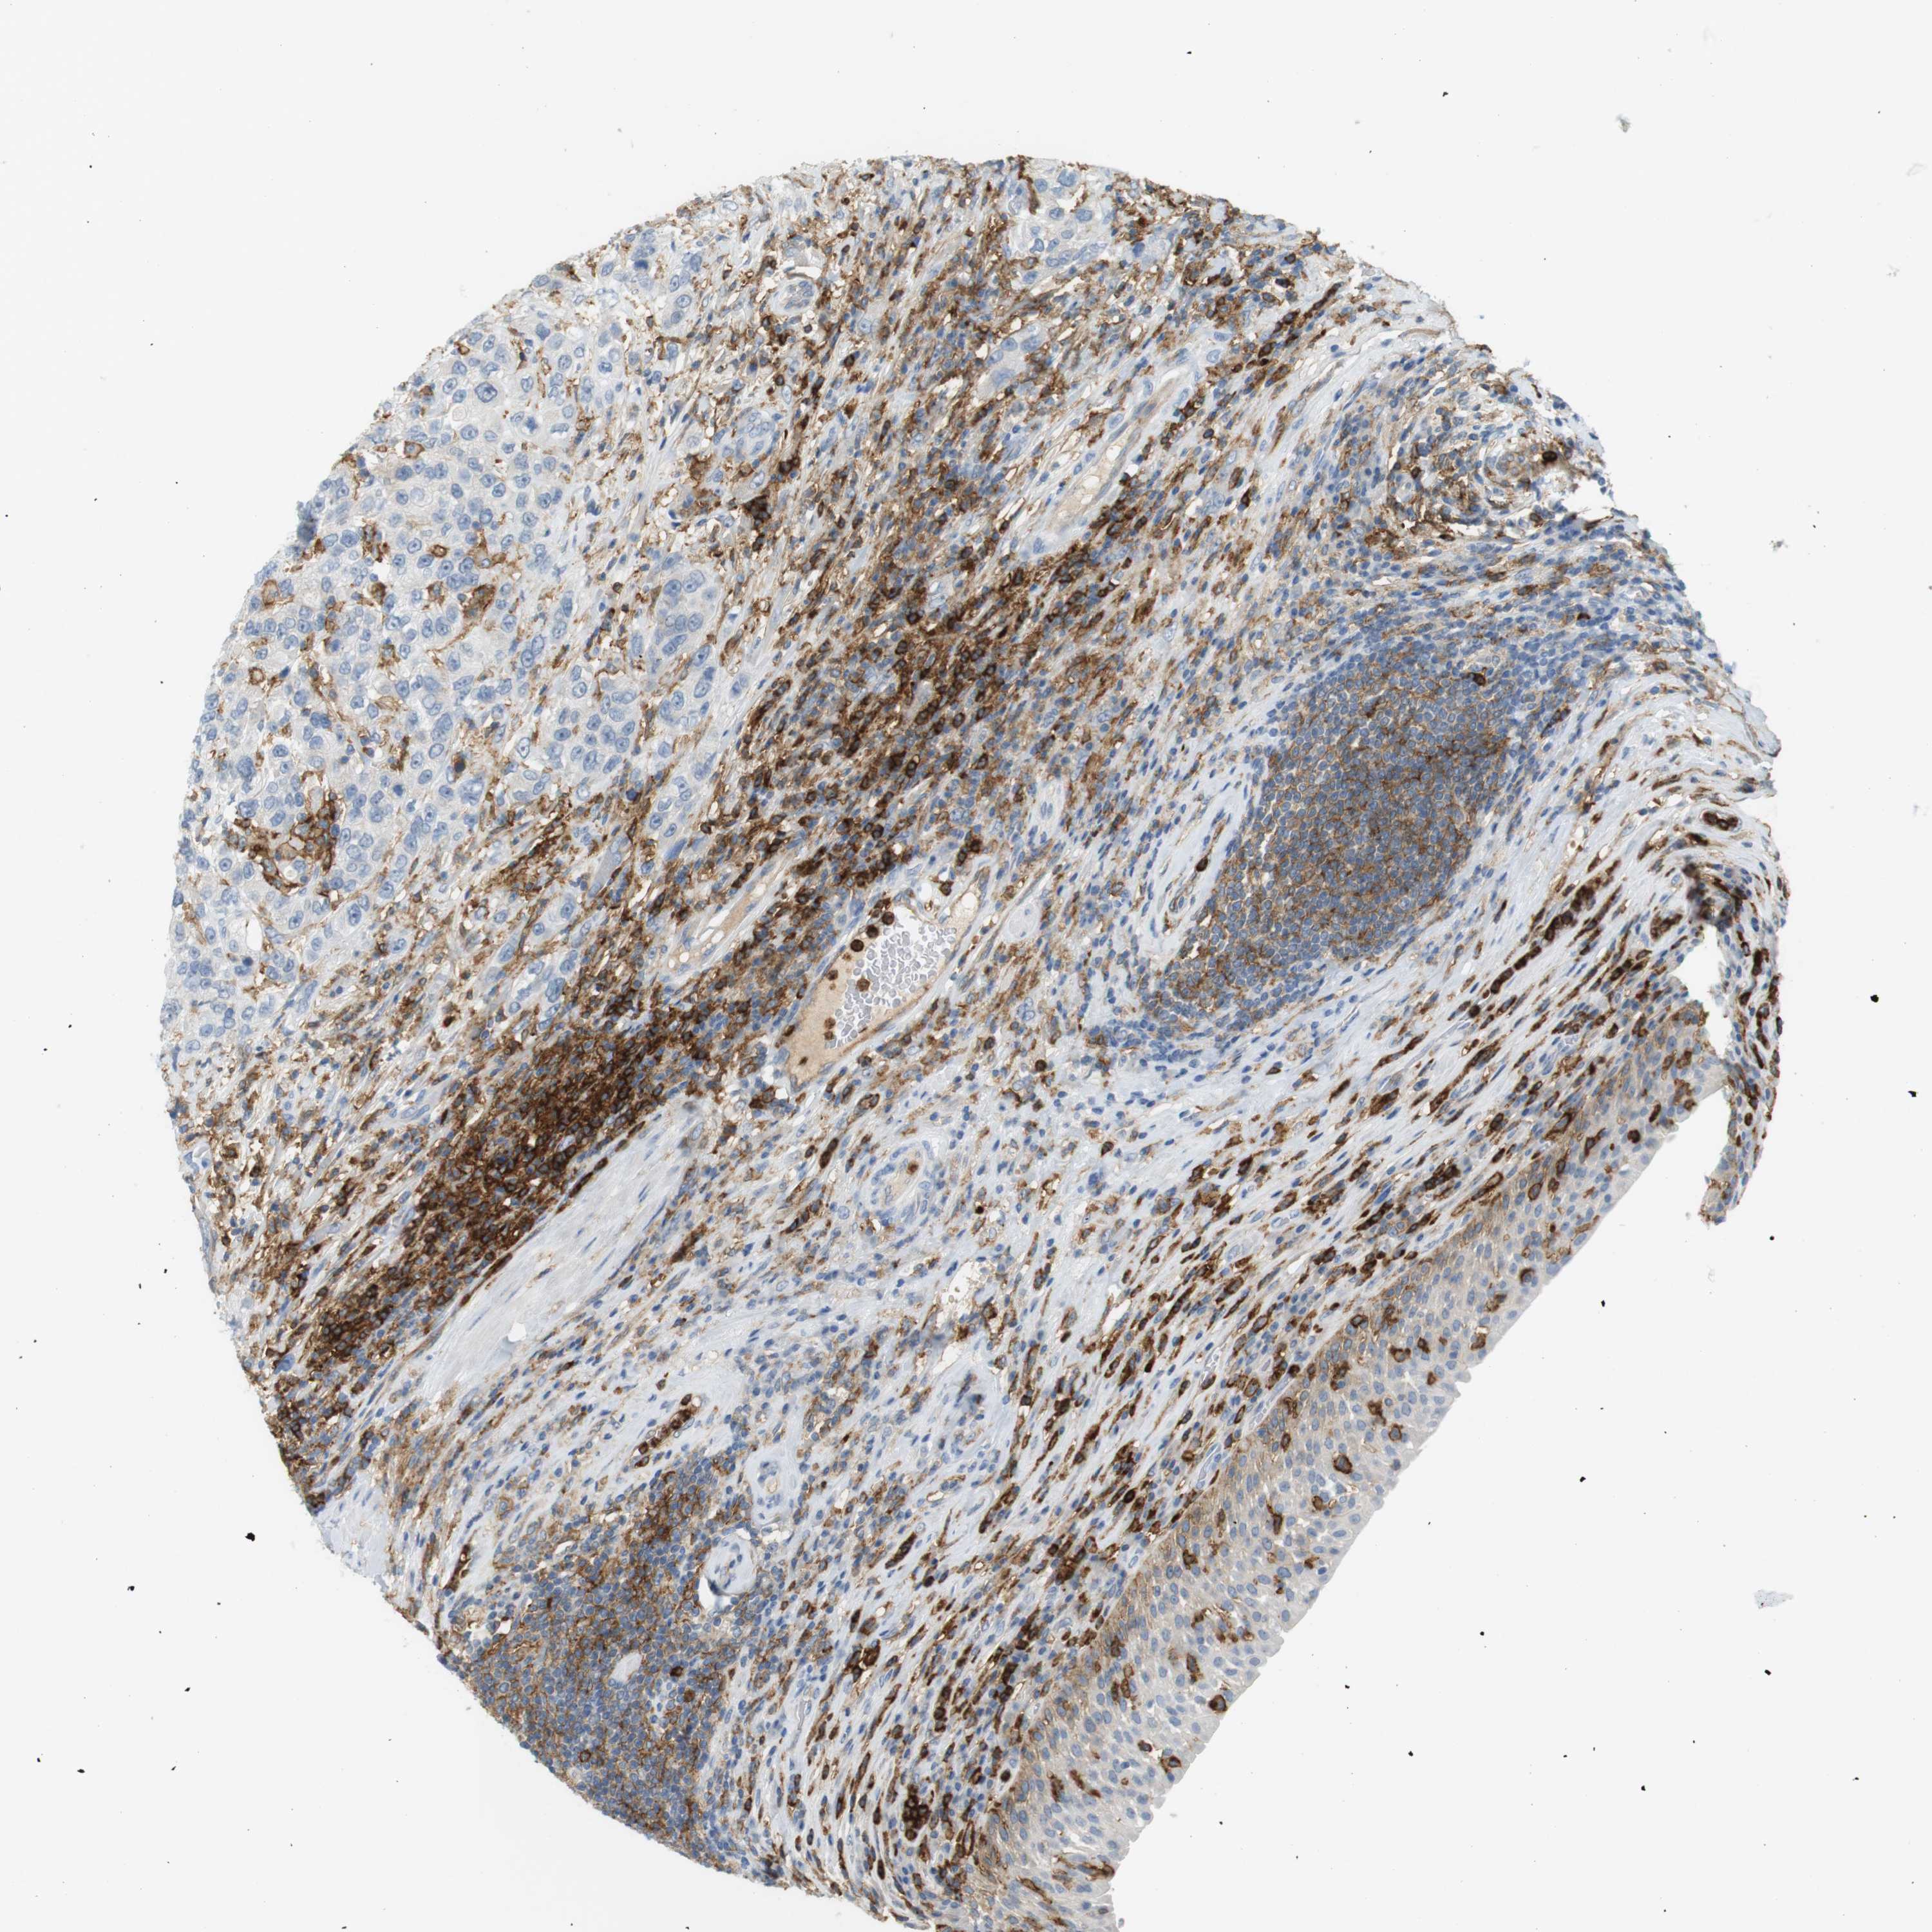

UROTHELIAL CANCER - Protein expressioni

A mouse-over function shows sample information and annotation data. Click on an image to view it in a full screen mode. Samples can be filtered based on level of antibody staining by selecting one or several of the following categories: high, medium, low and not detected. The assay and annotation is described here.

Antibody stainingi

Antibody staining in the annotated cell types in the current human tissue is reported as not detected, low, medium, or high, based on conventional immunohistochemistry profiling in selected tissues. This score is based on the combination of the staining intensity and fraction of stained cells.

Each image is clickable and will lead to virtual microscopy that enables deeper exploration of all samples and also displays staining intensity scores, fraction scores and subcellular localization as well as patient and tissue information for each sample.

Antibody HPA054437

Antibody HPA058511

Antibody CAB002776

Antibody CAB015122

Staining

High

Medium

Low

Not detected

Intensity

Strong

Moderate

Weak

Negative

Quantity

>75%

75%-25%

<25%

None

Location

Nuclear

Cytoplasmic/membranous

Cytoplasmic/membranous,nuclear

Urothelial carcinoma, High grade

Urothelial carcinoma, Low grade

Urothelial carcinoma, NOS